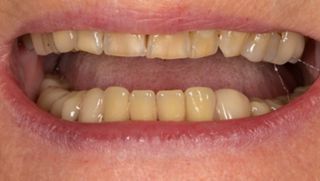

2a. View of the mouth showing limited gingival exposure.

2a